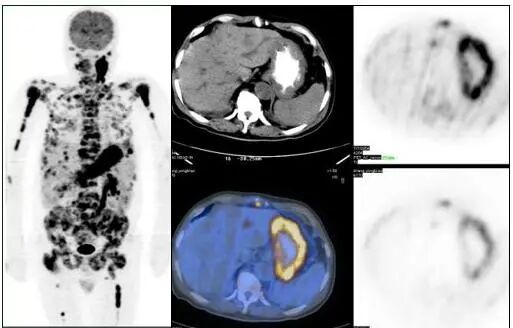

图片

胃癌全身广泛转移